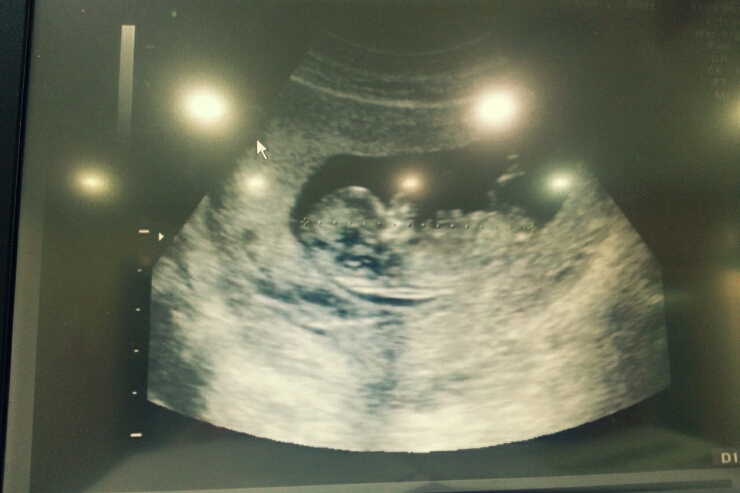

2014.06.19 홍시가 태어났어요.